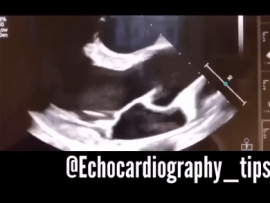

Lee mas45 years old female patient with congestive Heart Failure “EF=22%” and history of stroke , the Echocardiography shows multiple big thrombi in the Heart chambers and moderate pericardial effusion ..